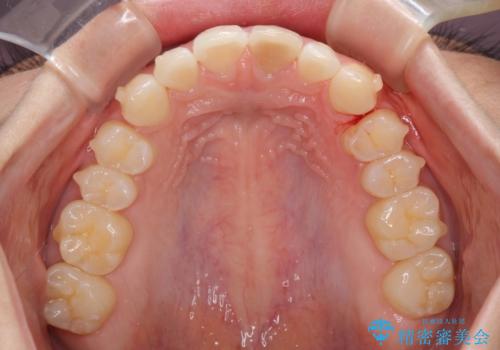

- 変色した前歯と突出した口元を気にして来院された患者様です。

口元の突出感はインビザラインにより歯列を整え、その後に、前歯をオーダーメイドタイプのオールセラミッククラウンにて補綴治療することとしました。

長時間のマウスピース装着と、患者様自身でのゴムかけに協力いただき、口元の突出感をしっかりと改善することができました。

前歯のオールセラミッククラウンもまるで本物の歯のように仕上がり、患者様には大変満足していただきました。